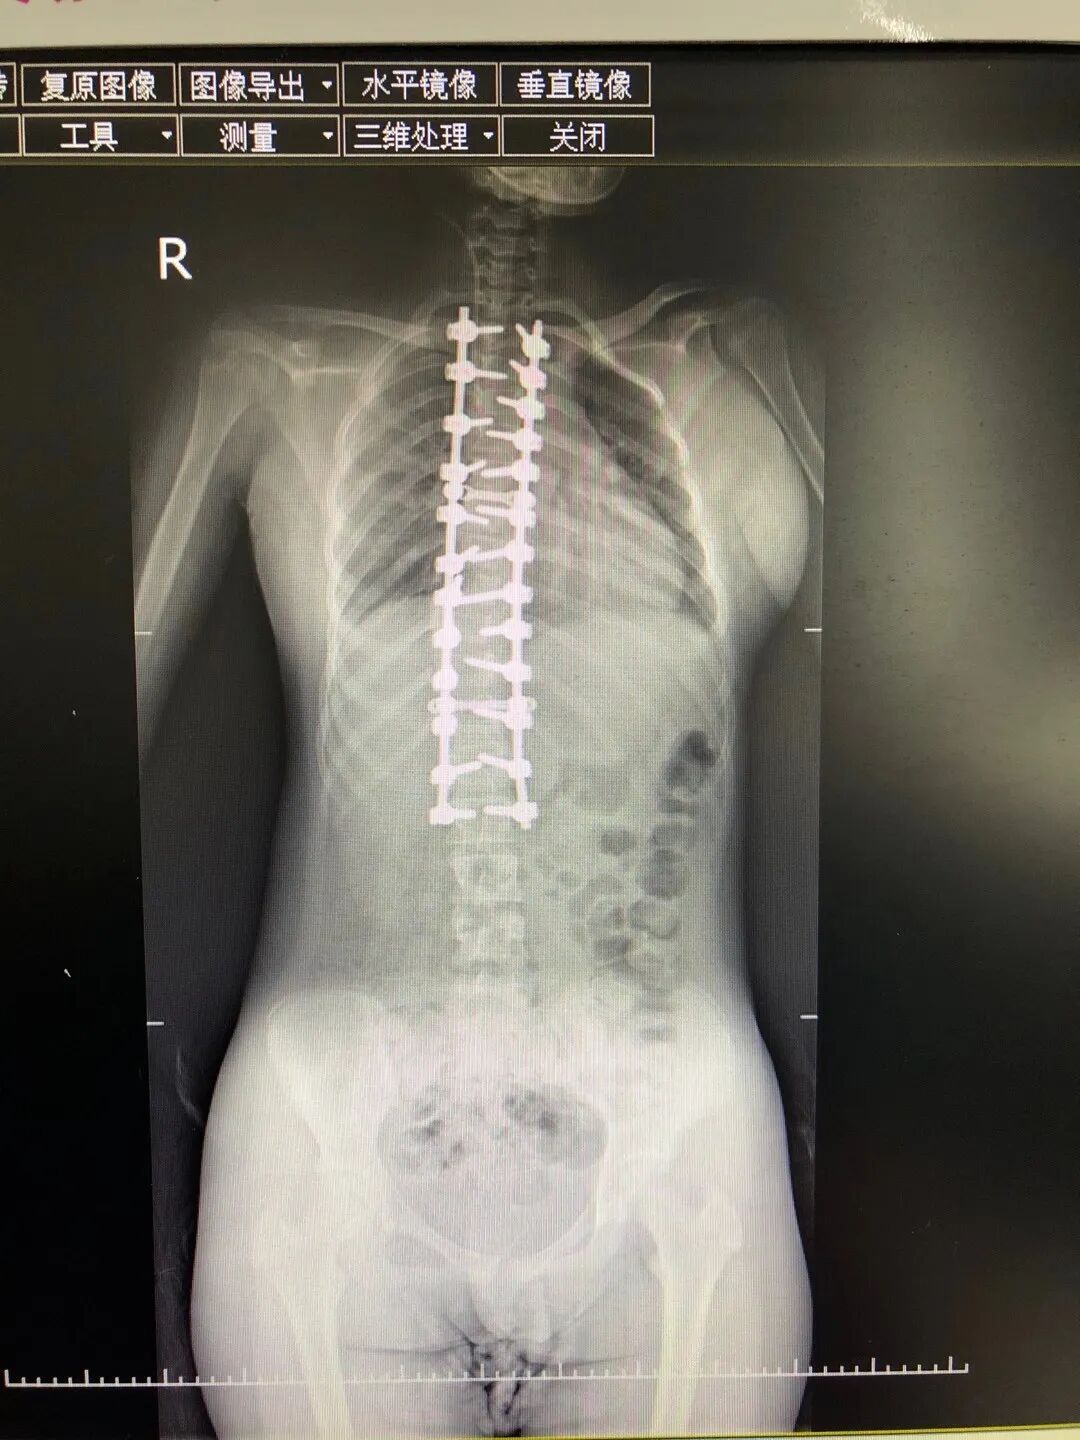

●13岁男孩的“挺胸”新生

初中生小伟(化名)因45°严重脊柱侧弯自卑度日,科室团队借助3D打印技术定制精准方案,完成三维矫形手术。术后他身高增5厘米,体态恢复正常,终于能像同龄人一样自信抬头。